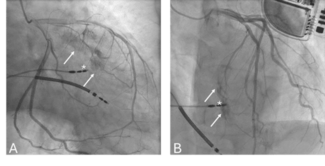

Brief Communication

Clinical Image